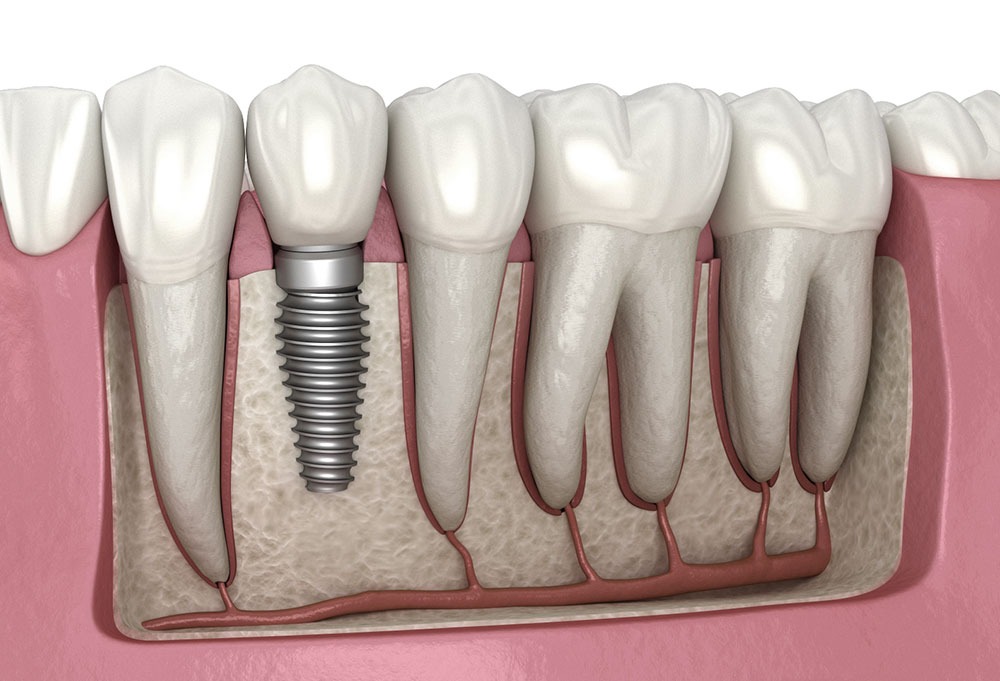

Dental Implants

Dental implants are reliable replacements for missing teeth. Designed to look, feel, and function like your natural teeth, implants are the preferred solution for single or multiple tooth loss. They also provide support for dentures, improving comfort and stability. Dental implants are a long-trusted method for restoring smiles with lasting results.